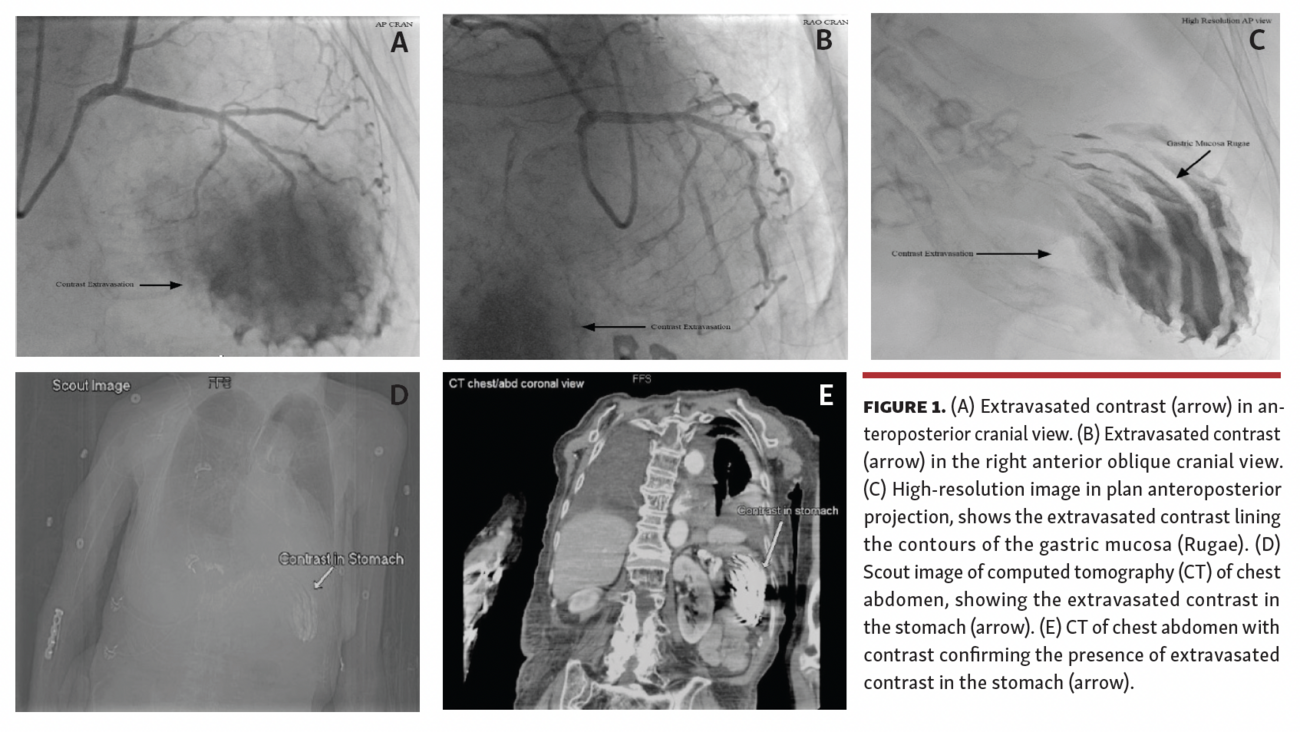

A 79-year-old woman presented with new-onset heart failure. She had pleural effusion, pericardial effusion, and an ejection fraction of 35% on echocardiogram. Her coronary angiogram revealed mild coronary artery disease (CAD). However, initially unexplained extravasation of the contrast was also seen in the cranial view during angiogram (Figures 1A and 1B). The decision was made to medically manage CAD, but she remained tachycardic, with borderline low blood pressure. A few hours later, she was taken back to the lab for pericardiocentesis, which drained only 20 mL of clear fluid. High-resolution fluoroscopic images showed an unusual and unexplained appearance of the contrast again, possibly in a subdiaphragmatic location (Figure 1C). She then developed melena. Computed tomography (CT) of the chest and abdomen with intravenous contrast confirmed the extravasated contrast concentrated in the stomach (Figures 1D and 1E). Endoscopy also showed the Cameron erosions in the hiatal hernia and “coffee ground” material in the stomach. Follow-up CT with contrast following stabilization of the patient confirmed the clearance of contrast from the stomach. This represents an unusual case in which fluoroscopy revealed active gastric bleeding with contrast extravasation during coronary angiography.